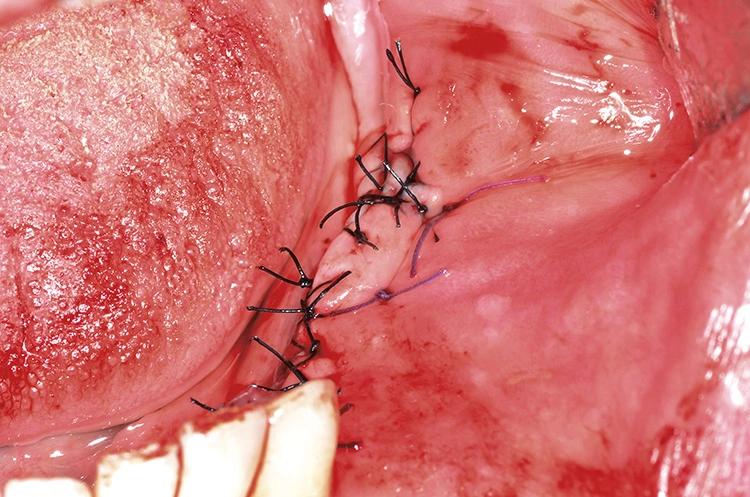

Augmentation

Tröltzsch

Tröltzsch Tröltzsch

Tröltzsch Tröltzsch

Tröltzsch Tröltzsch

Tröltzsch Tröltzsch

Tröltzsch Tröltzsch

Tröltzsch Tröltzsch

Tröltzsch Tröltzsch

Tröltzsch Tröltzsch

Tröltzsch